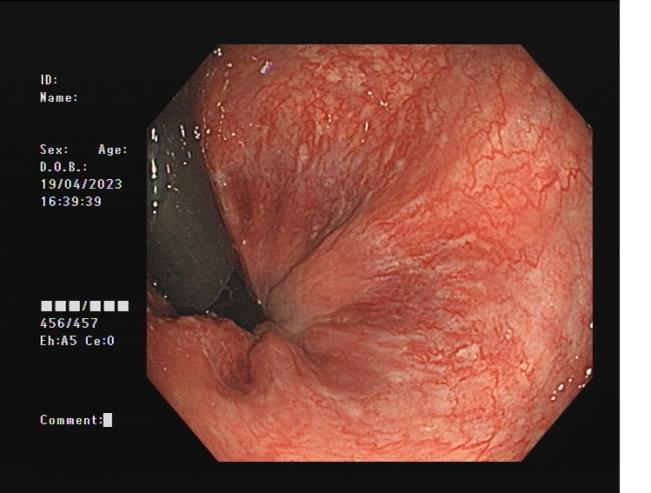

食管靜脈曲張             內(nèi)鏡下套扎術(shù)

食管靜脈曲張?zhí)自g(shù)(EVL):治療食管靜脈曲張、胃底靜脈曲張破裂出血、藥物止血無(wú)效者;既往有食管靜脈曲張破裂出血史者預(yù)防再出血。